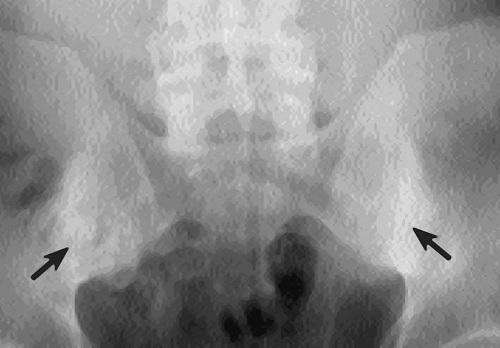

Остеосклероз на рентгене

- На рентгене при остеосклерозе видны тени от кости на фоне окружающих мягких тканей;

- Губчатое вещество внутри кости приобретает мелкопетлистую структуру (выглядит как множество мелких петель);

- Внутренний контур кости становится неровным;

- Костномозговой канал становится уже или даже исчезает полностью.

Очаги остеосклероза позвоночника, коленного, тазобедренного сустава имеют вид множества равномерно распределенных светлых пятен. Это пегий остеосклероз. При нем корковый слой не становится тоньше, а вот внутренний превращается в губчатый и рыхлый. Также есть ровный остеопороз. При нем остеосклеротические очаги выглядят прозрачными. В губчатом веществе визуально заметны трабекулы, то есть пластинки, перегородки.